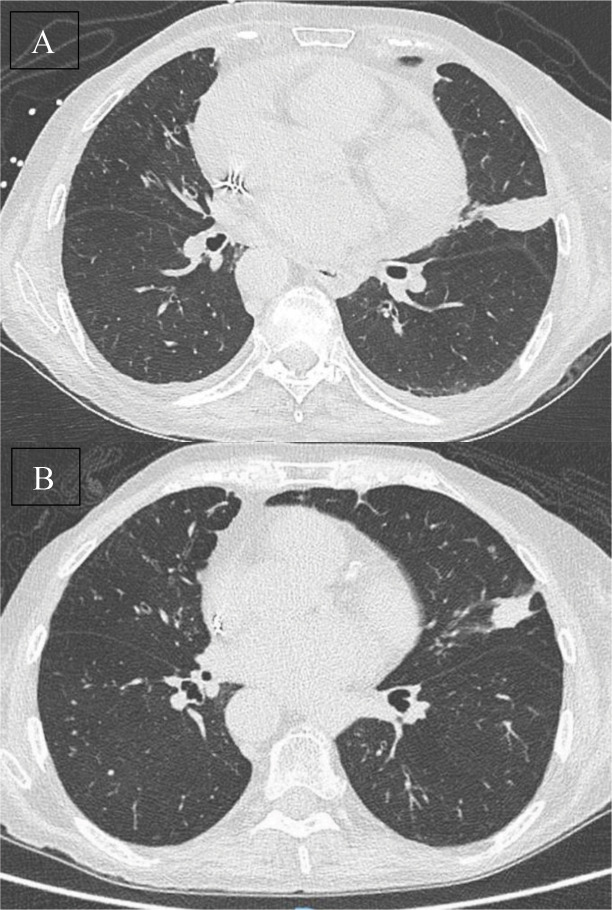

肺类癌是罕见的,可导致严重的副肿瘤综合征。本文报道一例78岁的ACTH依赖性库欣综合征患者不能手术,经微波消融术成功治疗。该手术导致临床迅速改善,无并发症和放射学稳定性。教学要点:微波消融术作为一种微创治疗选择,为不能手术的患者提供了一种有效的肿瘤控制策略。

Pulmonary carcinoid tumors are rare and may lead to severe paraneoplastic syndromes. A case is reported of an inoperable 78‑year‑old patient with ACTH‑dependent Cushing's syndrome successfully treated with microwave ablation. The procedure resulted in rapid clinical improvement without complications and radiological stability. Teaching point: The role of microwave ablation as a minimally invasive alternative for selected inoperable patients, offering an effective tumor control strategy with minimal morbidity.